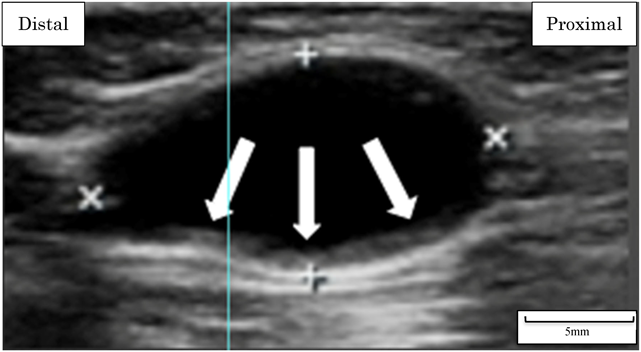

Fig. 2 Ultrasound imaging of the aneurysm

The ultrasound examination demonstrates a 10×8 mm (width×depth) aneurysm in the brachial artery. The arrows indicate a thrombus (clots) forming along the posterior wall.